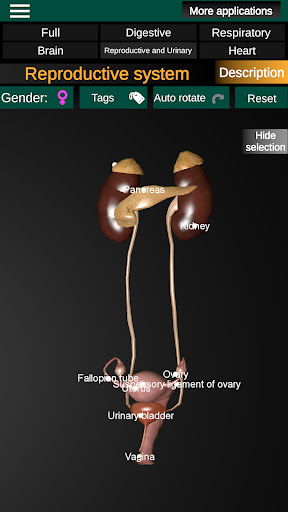

Internal Organs in 3D Anatomy لـ Vodafone Smart N9 Lite

(الأجهزة الداخلية في)

Internal Organs 3D Anatomy 3.4

يمكنك هنا تنزيل ملف حزمة تطبيق أندرويد "Internal Organs 3D Anatomy" الخاصة بجهازVodafone Smart N9 Lite مجانًا، نسخة ملف حزمة تطبيق أندرويد - 3.4 للتحميل على Vodafone Smart N9 Lite اضغط ببساطة على هذا الزر. إنه سهل وآمن. نحن نقدم فقط ملفات حزمة تطبيق أندرويد الأصلية. إذا انتهكت أية مواد موجودة في الموقع حقوقك قم بإبلاغنا من خلال